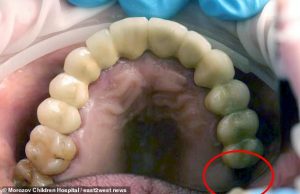

The hospital says ‘The tooth was the second molar or the seventh in the upper jaw.

‘It usually replaced by the permanent tooth at the age of ten to 12.’

A scan ‘revealed something inside the testicle that looked like renal gravel (gravel in kidneys).